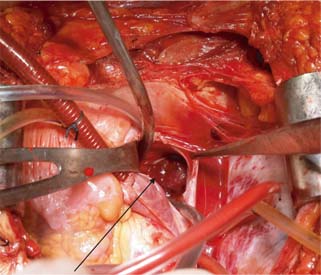

Figure 4: Opening of right atrium with arrow showing thrombus in situ.

The surgical technique used for different levels of thrombus extension in our study is as follows. For level I (Figure 1) thrombus, vascular side clamps are used without occluding IVC inflow. The cavotomy defect is then sewn using a continuous prolene 4-0 suture. Level II thrombus (Figure 2A and B) often necessitates more extensive mobilization of the IVC. Proximal and distal control of IVC is necessary with ligation and division of lumbar veins to prevent significant blood loss. For the retrieval of thrombus, vascular clamps are used with clamping of the left renal vein in case of right-sided renal tumors and clamping of the right renal artery in case of left-sided renal tumors. The cavotomy defect is sewn using continuous prolene 4-0 suture. For level IV thrombi (Figure 3), a beating heart surgery with a simplified CPB technique was used for retrieval of thrombus from RA. For level IV thrombi, ligation of renal artery is followed by radical nephrectomy using chevron incision. The left renal vein is looped, and IVC below the renal vein is skeletonized for a length of about 5 cm to prepare it for IVC cannulation. A purse string is made on it using 4-0 prolene monofilament suture and the subhepatic portion of IVC is dissected. Then, median sternotomy is performed and pericardium is opened. Aortic purse-string suture with 3-0 prolene is taken on the ascending aorta. The intrapericardial portion of the superior vena cava (SVC) is looped, and a purse-string with 3-0 prolene is taken. Patient is heparinized with 300 Units/kg body weight of heparin. Aortic and venous cannulations are performed, and patient is put on complete CPB after both SVC and IVC are snugged with Rummel tourniquet. No vent cannula is put in. Patient is cooled to 35°C. On beating heart under normothermic CPB, RA thrombus (Figure 4) is extracted without cross-clamping the aorta. Right atriotomy is performed and tumor thrombus, which is organized and firm, is carefully retrieved. IVC is snugged at its junction with RA to prevent spillover from IVC into RA. Subhepatic IVC is incised longitudinally, and the tumor thrombus is extracted, using digital manipulation to ensure complete removal from retrohepatic IVC. Intermittent suctioning is performed using a pump sucker as hepatic veins are opened up. Cavotomy is closed using 4-0 prolene suture. After completely de-airing the RA, the atriotomy is also closed. Patient is gradually weaned off the bypass. “Patients were followed up quarterly in the first year, semiannually in the second year, and annually thereafter”.